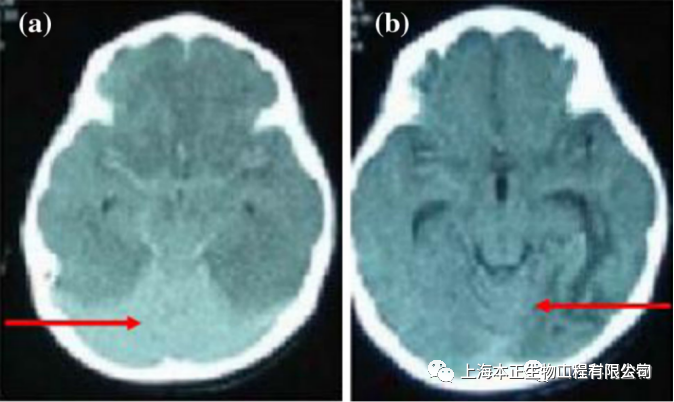

上海本正干细胞实验室对6MS患者进行了间充质干细胞治疗,并进行了2年的随访追踪,显示出患者的神经功能得到改善,视觉障碍,手臂、腿或脸部麻木刺痛,疲劳、肌肉无力和痉挛等明显好转。表面间充质干细胞治疗MS是可行和有效的。

左治疗前,右治疗后